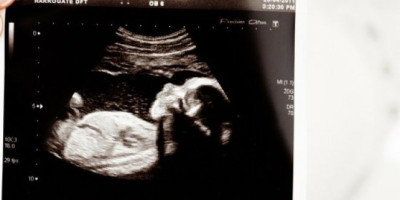

Na svetskom nivou je zabeleženo samo 13 slučajeva superfetacije pre rođenja Rozalije i Noe u septembru prošle godine. Rebeka je izjavila da je imala emotivni ringišpil jer je imala osećaj da lekari pokušavaju da dokažu da nešto nije u redu sa jednim od blizanaca jer je superfetacija veoma retka i neobična pojava. Oni su mislili na sitnijeg blizanca.

Ona i njen partner Ris Viver su saznali da će dobiti bebu još u februaru prošle godine, pre prvog zaključavanja Velike Britanije.

- Ponudili su mi rano snimanje sa sedam nedelja i Ris je mogao da prisustvuje jer su bolnice tada bile otvorene. Videli smo našu malu bebu koja je bila veoma sitna i majušna. Rečeno nam je da čekamo jedno dete. Posle nekoliko nedelja, imala sam pregled i ultrazvuk u 12. nedelji trudnoće. Tada Risu nije bilo dozvoljeno da bude u bolnici jer je karantin počeo - kaže Rebeka.

Ova mama iz Troubridža u okrugu Vitšir u Engleskoj je doživela šok kada su joj rekli da čeka blizance, ali su stvari postale još neverovatnije.

- Bilo je veoma očigledno da je jedan blizanac mnogo veći od drugog. Među njima je bila razlika u veličini od tri nedelje. Nisu mogli da razumeju šta se događa i zašto je razlika u veličini tako velika. Nakon brojnih pregleda, specijalista za blizance iz bolnice je došao do zaključka da sam ponovno ovulirala. U osnovi sam zatrudnela dok sam bila trudna - rekla je Rebeka.

Bili su veoma iznenađeni onim što su čuli, a onda je Rebeka otišla kući i tražila na Internetu pojam superfetacija. Paru je rečeno da je ova pojava veoma retka i da ih ima samo 13 na celom svetu. Rebeka ima i ćerku Samer (14) iz prethodne veze, a svi su bili zabrinuti jer neki doktori nisu bili sigurni da je dijagnoza dobra. Bili su zabrinuti da sa manjom bebom nešto nije u redu ili se ne razvija pravilno.

- Bilo je to kao da su pokušavali da dokažu da nešto nije u redu, bili su uvereni da to nije superfetacija. Naš se svet srušio, nisam uopše mogla da uživam u trudnoći, sve stvari u kojima bi trebalo da uživate su nestale. Bilo je vrlo, vrlo zastrašujuće. Bio je to period stalnih uspona i padova. Kad nam je doktor rekao da ne misli da je to superfetacija, to nas je baš pogodilo - ispričala je.

Doktori su primetili da postoji problem s pupčanom vrpcom blizanaca, pa je Rebeka primljena na carski rez u 33. nedelji trudnoće. Blizanci su rođeni 17. septembra. Noa je rođen sa 2,1 kg, a Rozalija sa 1,1 kilograma. Bebe su prve dve i po nedelje života provele odvojene jer je Noa boravio u bolnici Bat, a Rozalija je odvedena na posebnu negu u Bristol, pa su mama i tata morali da dele vreme između svoje dve bebe u odvojenim gradovima.

Dve nedelje kasnije mala Rozalija je prebačena nazad u Bat bolnicu kako bi se ponovno srela sa svojim bratom Noom. Noa je proveo tri nedelje i tri dana na neonatalnoj intenzivnoj nezi, a Rozalija je tamo provela 95 dana pre nego što joj je napokon dozvoljeno da ode kući nešto malo pre Božića. Sve do skoro, njihovi roditelji su izbegavali da pričaju sa prijateljima i široj familiji o njihovom rođenju, a kada su konačno postali sigurni da su bebe dobro. Rebeka sada dokumentira svoje blizance začete superfetacijom na svojoj Instagram stranici gdje dijeli slike i novosti o njima.

- Previše smo se bojali da bismo bilo šta rekli. Obavestili smo samo bližu porodicu i bili smo veoma oprezni samo zato što smo se plašili da se nešto ne desi. Međutim, ipak je nešto dobro izašlo iz 2020. godine. To je najfascinantnije i najneverovatnije čudo koje se desilo baš nama. Osećam se mnogo srećnom. Naš prijatelj je rekao da se Rozalija izborila za svoje mesto u svetu i da je to znak da je i trebalo da bude ovde - zaključila je mama troje dece.